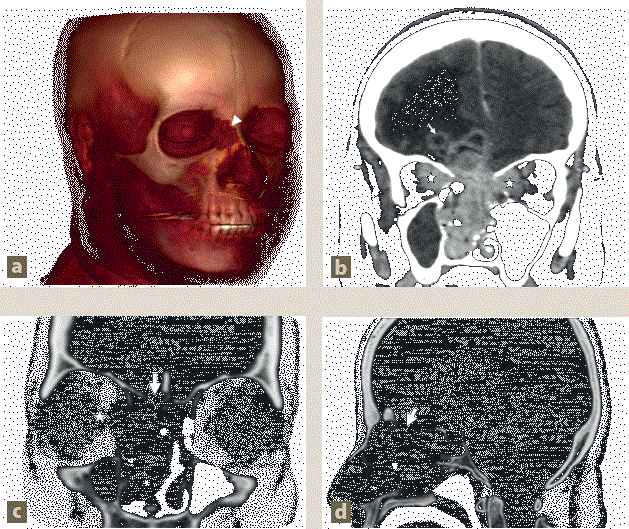

Se le realizó una tomografía simple de cráneo, en la cual se observaron celdillas etmoidales, senos frontales y esfenoidales ocupados por una zona hipodensa, con realce homogéneo en la fase contrastada, con extensión al cornete inferior derecho, lo que condicionaba obstrucción del antro maxilar derecho y resorción ósea en las celdillas etmoidales, así como en la pared medial del seno maxilar ipsilateral. Se observó una solución de continuidad del hueso etmoides, con extensión de la lesión al parénquima cerebral. El parénquima cerebral mostraba una imagen en el giro frontal derecho, de 10.2 × 6.9 mm, con bordes hiperdensos, centro de menor densidad, realce de atenuación, desviación de la línea media de 5 mm y disminución del ventrículo lateral, con edema perilesional (figura 1).

Imagen: Prado Hernández et al.

Figura 1 Tumor nasal con extensión intracraneal. a) Reconstrucción 3D que muestra pérdida de integridad en el hueso nasal derecho (punta de flecha). b) tomografía computarizada (TC) contrastada en corte coronal, donde se observa el tumor nasal con extensión intraorbitaria (asteriscos) y extensión intracraneal en forma de imágenes quísticas con realce en anillo (flechas delgadas). c) y d) TC con algoritmo óseo en cortes coronal y sagital, respectivamente, evidenciando pérdida de integridad en la lámina cribiforme (flechas gruesas) y en las láminas papiráceas (asteriscos).